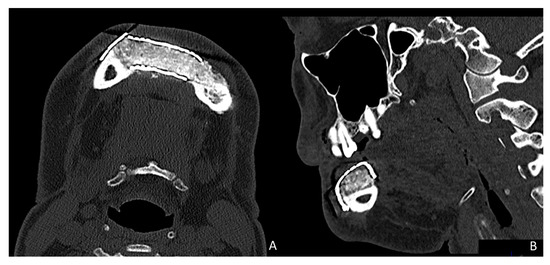

CT Scan and CBCT were performed in the postoperative follow-up, and bone volume and bone resorption (Figure 13 and Figure 14) were evaluated by the Radiology Department of the hospital. A morphing reconstruction was performed to compare the lower facial third showing an improvement in the aesthetic profile and facial projection (Figure 15).

Figure 14. CBCT performed in the follow-up to evaluate bone resorption before and after implant loading.